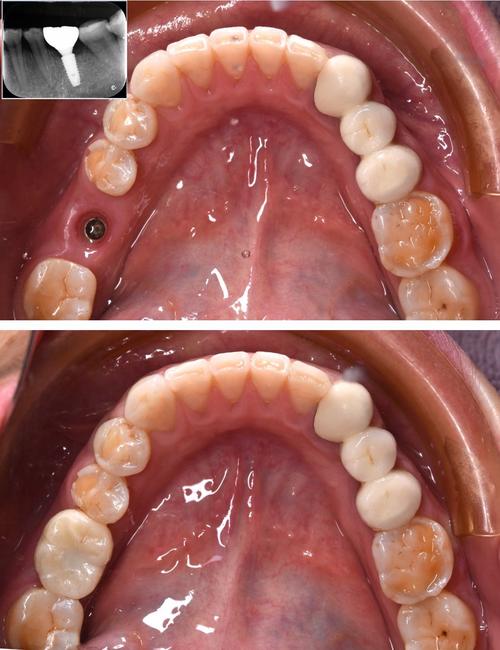

不同位置的缺牙,手术难度差异显著,前牙区(门牙等)骨质通常较厚,距离重要解剖结构(如下牙槽神经、上颌窦)较远,操作空间充足,难度较低;后牙区(磨牙等)骨质较疏松,且靠近上颌窦(上颌后牙)和下颌神经管(下颌后牙),若种植体位置偏差,可能穿透上颌窦或损伤神经,导致出血、麻木等并发症,对医生的技术要求更高。

缺牙数量同样影响难度:单颗牙缺失只需植入1颗种植体,手术时间短(通常30-60分钟);多颗牙缺失或全口无牙,可能采用All-on-4等技术,需精确设计种植体角度和分布,手术时间更长(2-4小时),技术更复杂。

常规种植手术(即“延期种植”)是在拔牙后3-6个月,待牙槽骨愈合后进行,步骤相对简单,但若存在拔牙创感染、骨缺损、即刻种植(拔牙同时植入种植体)等情况,则需附加治疗,上颌窦内提升(骨量不足时,从内侧推高上颌窦黏膜并植入骨粉)、骨劈开(狭窄牙槽骨纵向劈开以扩大种植空间)、引导骨再生(GBR,用膜材料防止骨组织被软组织侵入)等,这些技术操作精细,需医生具备扎实的解剖知识和外科功底,难度显著增加。